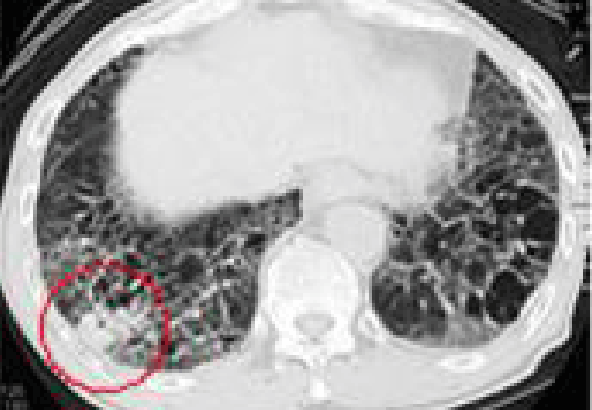

석면폐증(잠복기 약 15~40년)

잠복기가 약 15~40년에 걸친 석면으로 인한 석면폐증에 대한 CT사진

석면에 의한 폐 조직에 상처로 나타나는 폐섬유화 증상

• 폐의 섬유화로 희게 나타나며 공기집이 생겨 벌집모양으로 나타남

석면폐증의 병 유형(의심형, 초기형, 진행형) 및 폐기능 장해단계(정상, 경도장해, 고도장해)에 따라 1~3급으로 구분

• 석면폐증의 병 유형 : 폐섬유화 소견에 따라 의심형, 초기형, 진행형으로 구분

폐섬유화 소견에 따른 의심형 이미지 〈의심형〉

폐섬유화 소견에 따른 초기형 이미지 〈초기형〉

폐섬유화 소견에 따른 진행형 이미지 〈진행형〉